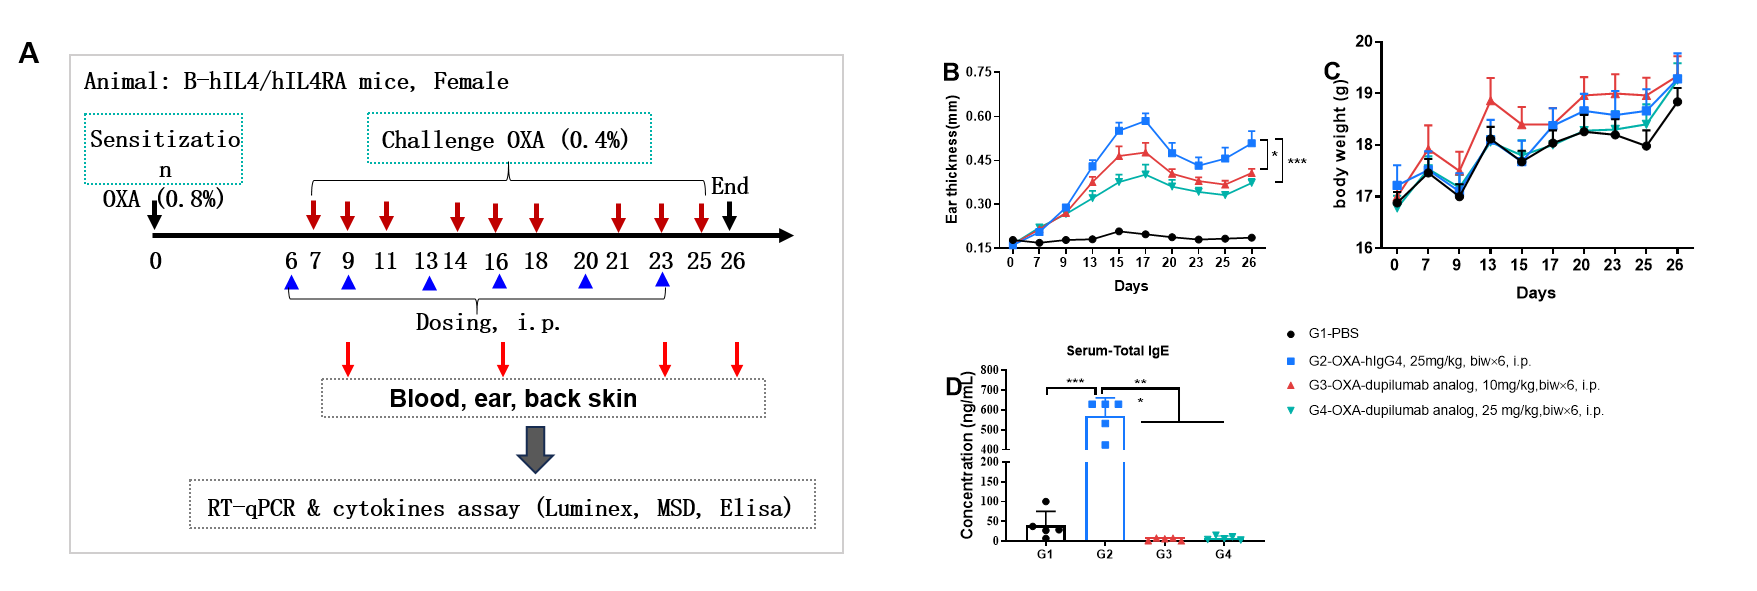

Dupilumab (in house) alleviated OXA induced atopic dermatitis in B-hIL4/IL4RA mice. Mice received 0.8% OXA on ear and skin on day 0, then received 0.4% OXA application three times a week from day 7 to day 25. Body weight and ear thickness were recorded after OXA application. Mice received PBS or dupilumab(in house) (10, 25 mg/kg) twice a week from day 6 for totally 6 times. Ear, back skin and blood were collected at the end (A). Dupilumab produced no effects on body weight (C). Ear thickness (B) and serum IgE (D) were decreased in dupilumab treated mice.

Efficacy of anti-human IL4RA antibody in B-hIL4/hIL4RA mice. Mice in each group were treated with different dose of dupilumab produced in house. Doses are shown in legend. (A) Body weight changes during treatment. (B) Statistical analysis of ear thickness in each group. Epidermis of ear began to desquamate from day 18. So the ear thickness was decreased from day 18 as shown in figure. (C) Total IgE levels in serum. Total IgE levels were measured by ELISA on day 26. Ear thickness and concentrations of total serum IgE were negative related with the doses of antibody. (n = 5).

Efficacy of anti-human IL4RA antibody in B-hIL4/hIL4RA mice. Mice in each group were treated with dupilumab (in house) produced in house. Doses are shown in legend. (A) Body weight changes during treatment. (B) Statistical analysis of ear thickness in each group. Epidermis of ear began to desquamate from day 18. So the ear thickness was decreased from day 18 as shown in figure. (C) Total IgE levels in serum. Total IgE levels were measured by ELISA on day 26. Ear thickness and concentrations of total serum IgE were negative related with the doses of antibody. (n = 5).